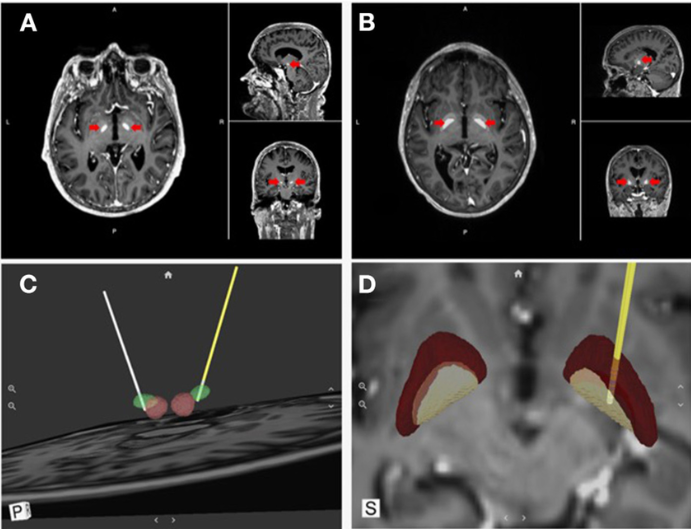

既然开关坏了,那就修开关。希斯拎起电钻,在病人的脑壳上钻开几个洞,直接把几根细长的电极插进了大脑深处一个叫「伏隔核」(Septal Area)的地方。

他给病人配了一个便携式的按钮盒,只要病人感到痛苦或幻觉发作,按一下,微电流就会瞬间击中大脑的快感中心——让病人暂时摆脱痛苦,获得短暂的愉悦。

希斯一生的「挚爱」-伏隔核具体位置示意图